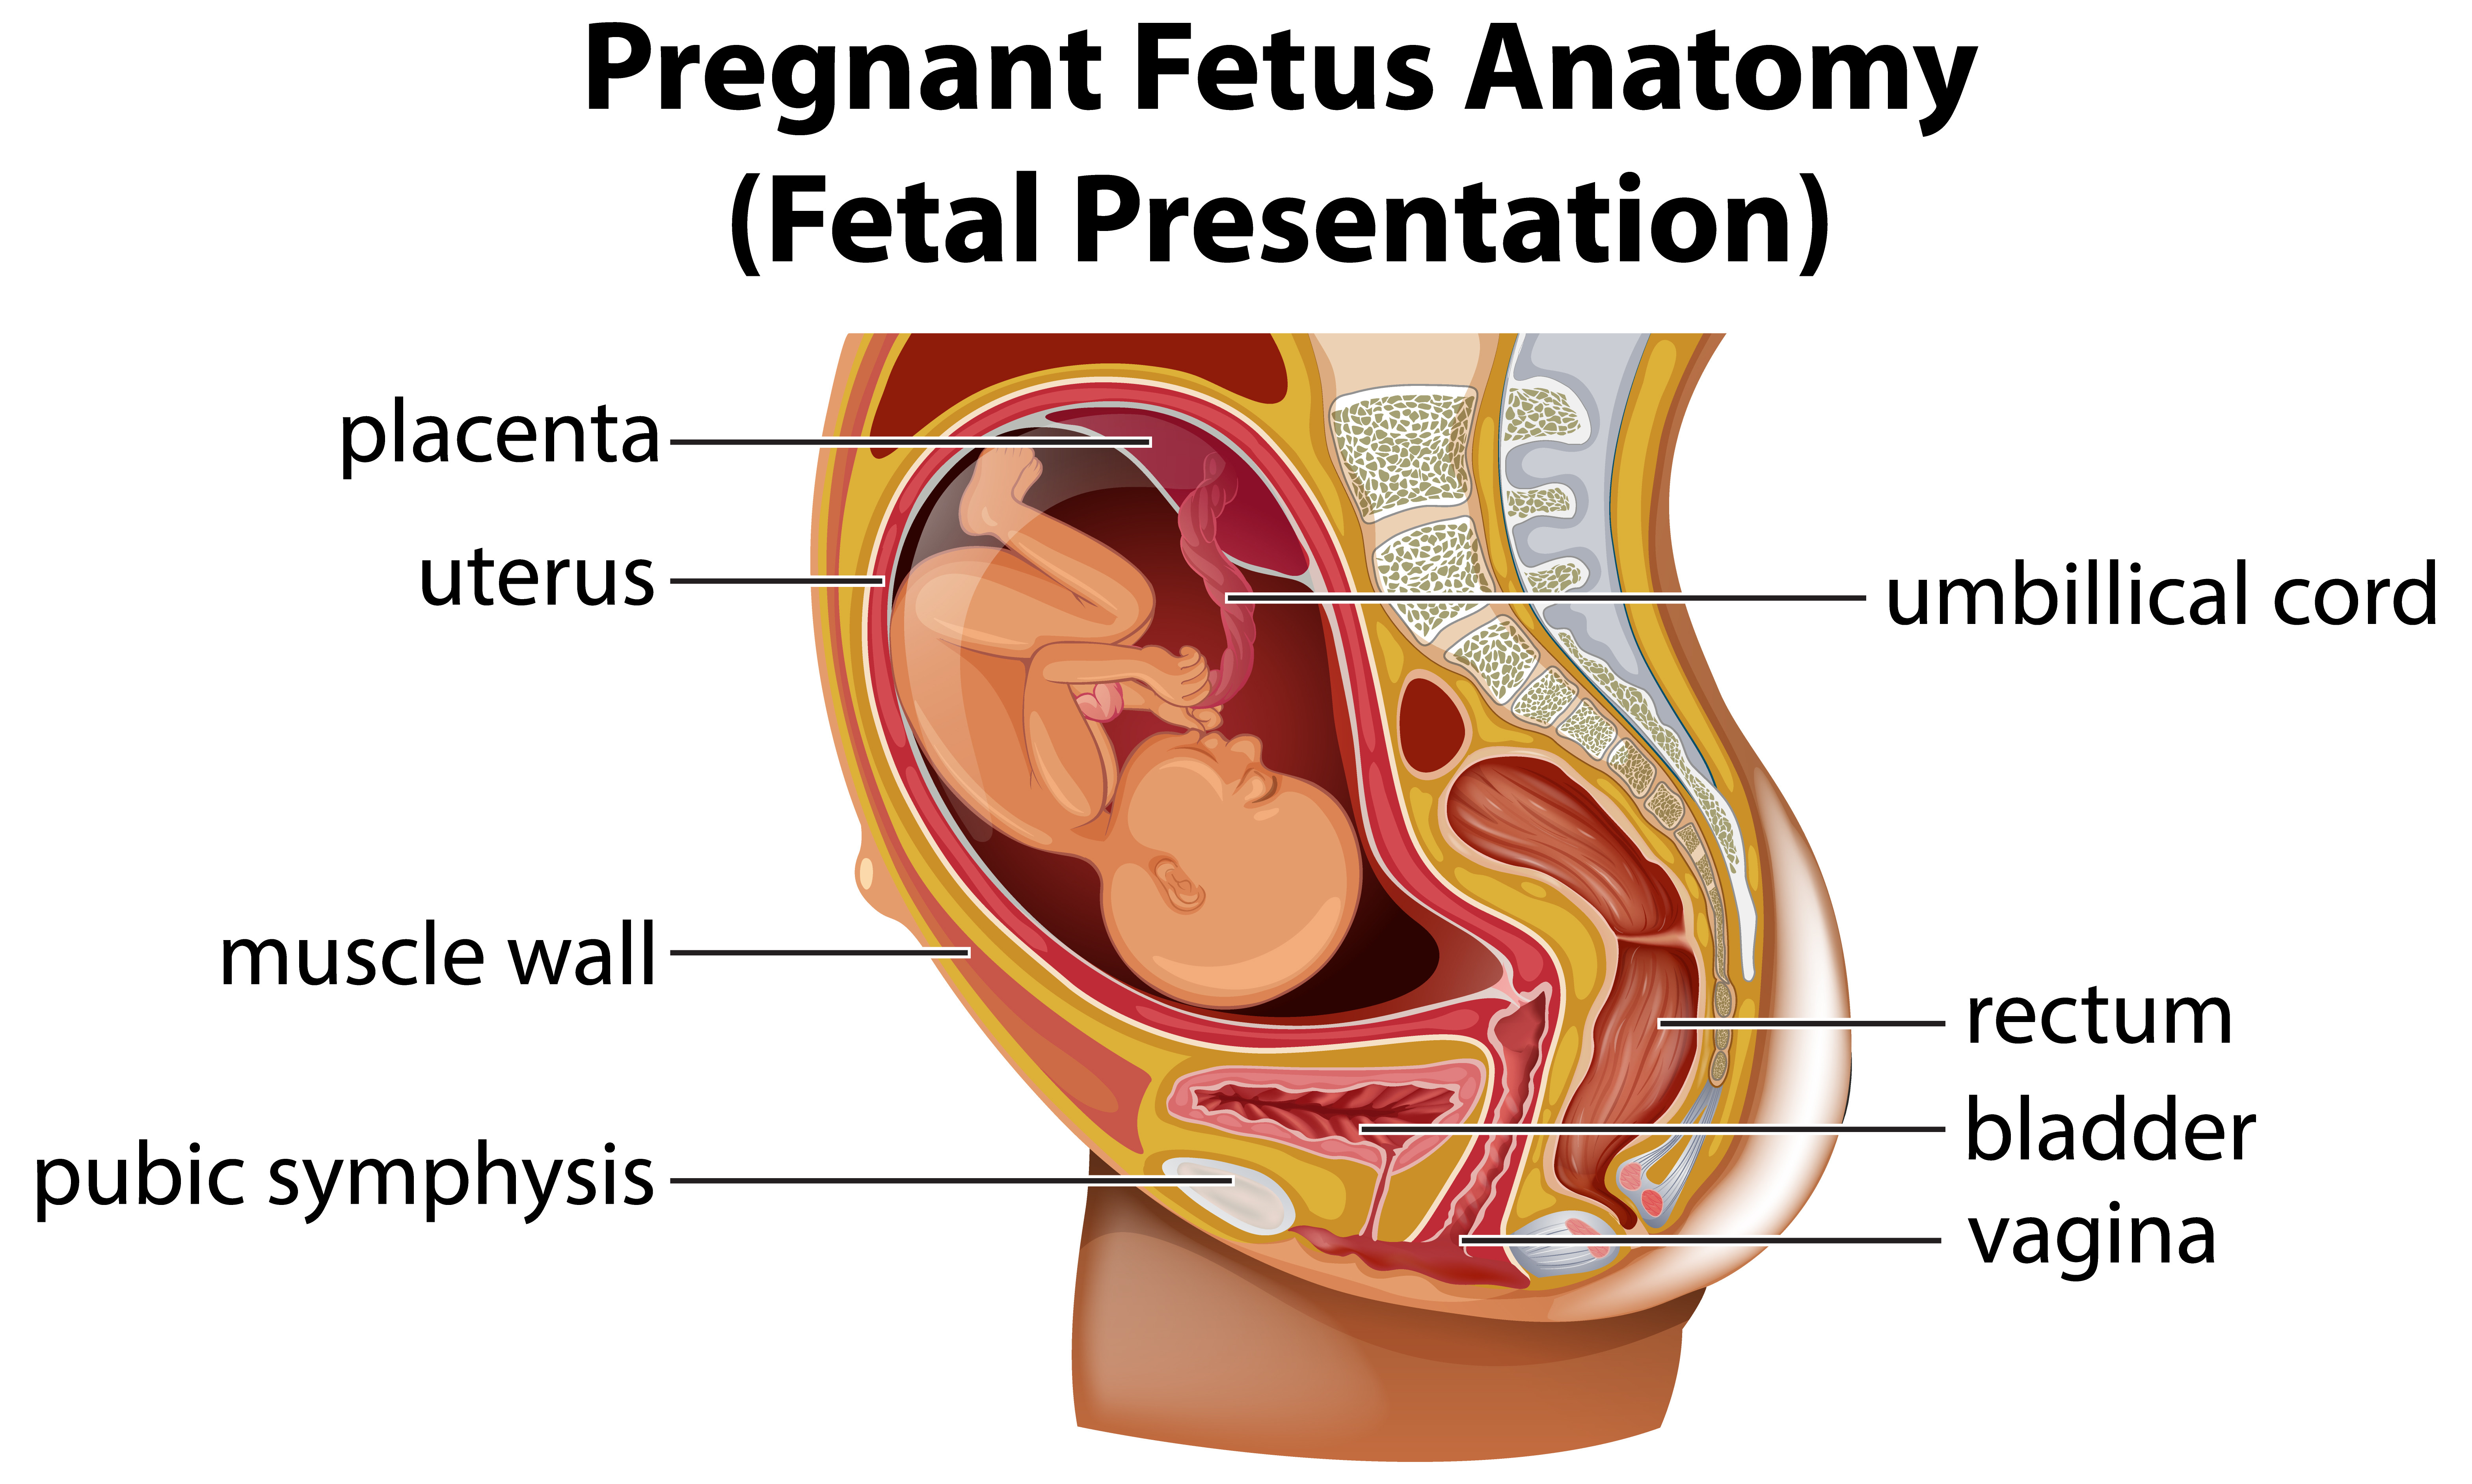

Insufisiensi Plasenta

Insufisiensi plasenta adalah kondisi medis di mana oksigen dan nutrisi tidak dapat masuk secara cukup ke dalam janin melalui plasenta.

Plasenta Previa

Plasenta previa adalah suatu kondisi kehamilan dimana plasenta menutupi leher rahim secara komplit atau sebagian